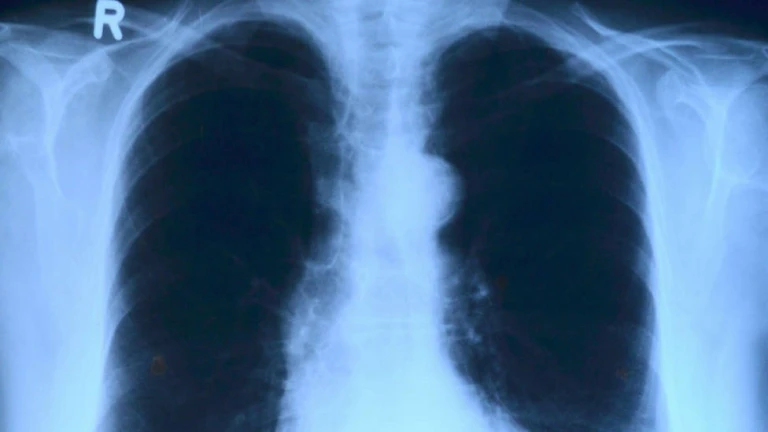

Una ecografía del tórax puede ayudar a detectar el coronavirus

El neumólogo Javier Pérez ha descubierto que una ecografía en el tórax ayudar a detectar el virus: "Estamos viendo que a los fumadores les afecta más"